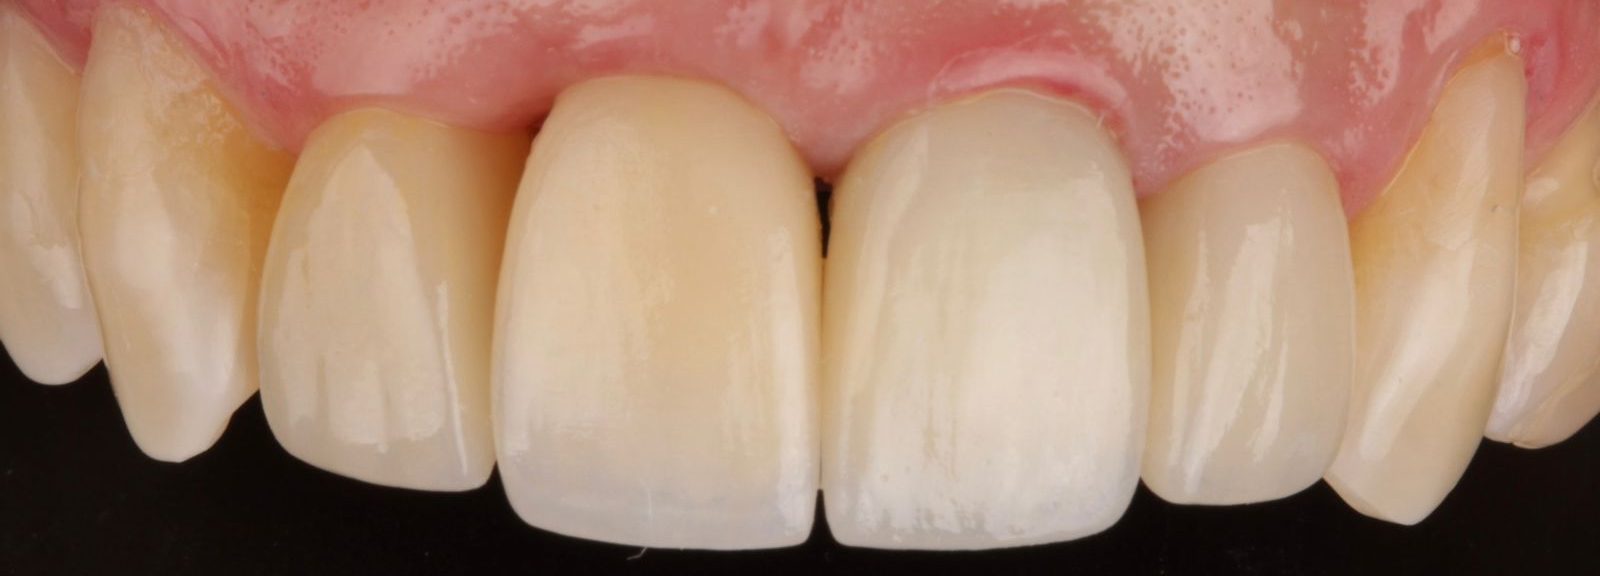

Fase rehabilitadora

Esta fase incluye todos los procedimientos para la elaboración de la prótesis definitiva, lo que puede implicar una serie de citas donde se buscará alcanzar los mejores resultados estéticos y funcionales.